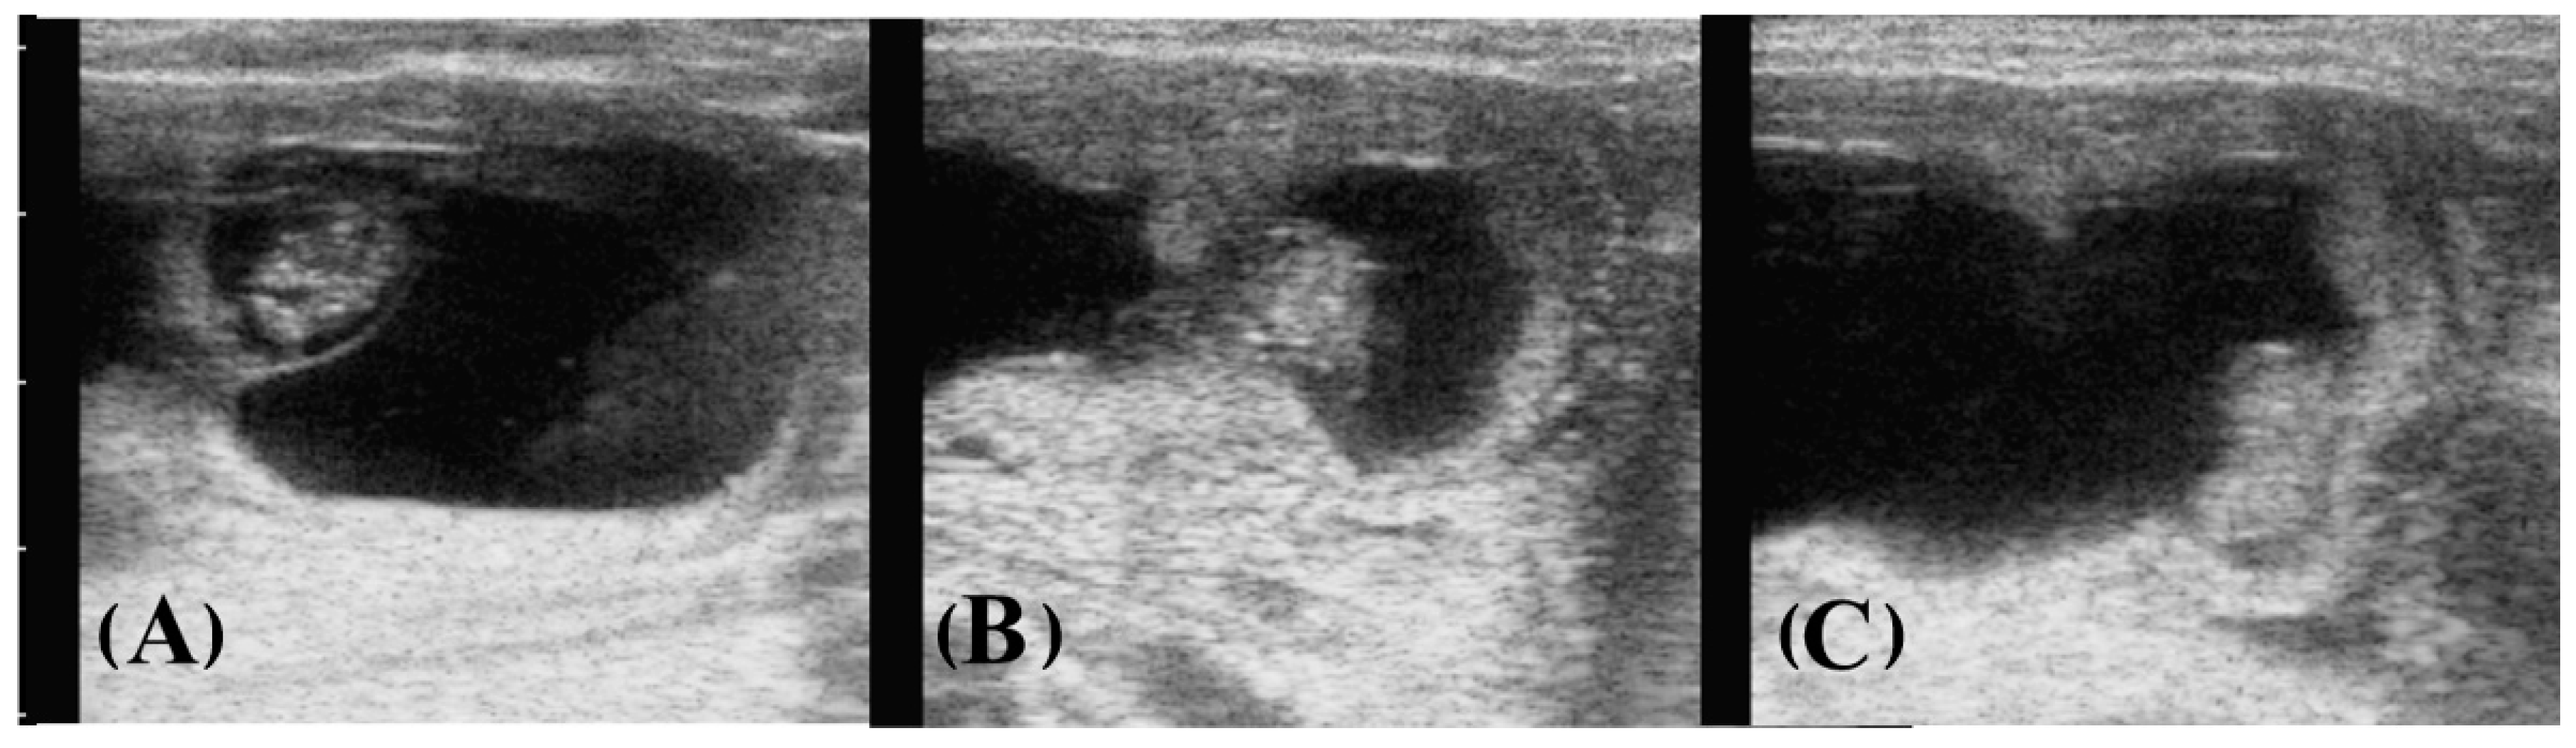

- Müller, E.; Wittkowski, G. Visualization of male and female characteristics of bovine fetuses by real-time ultrasonics. Theriogenology 1986, 25, 571–574. [Google Scholar] [CrossRef] [PubMed]

- Curran, S.; Kastelic, J.P.; Ginther, O.J. Determining sex of the bovine fetus by ultrasonic assessment of the relative location of the genital tubercle. Anim. Reprod. Sci. 1989, 19, 217–227. [Google Scholar] [CrossRef]

- Stroud, B.K. Using ultrasonography to determine bovine fetal sex. Vet. Med. 1996, 91, 663–672. [Google Scholar]